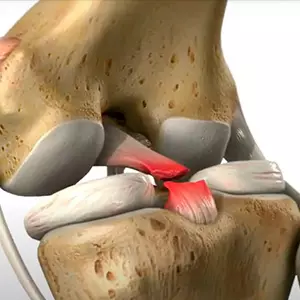

Reconstrucción del ligamento de la rodilla

Los ligamentos de la rodilla se pueden reparar quirúrgicamente mediante el uso de un pedazo de tendón sano del propio cuerpo del paciente o de un donante.